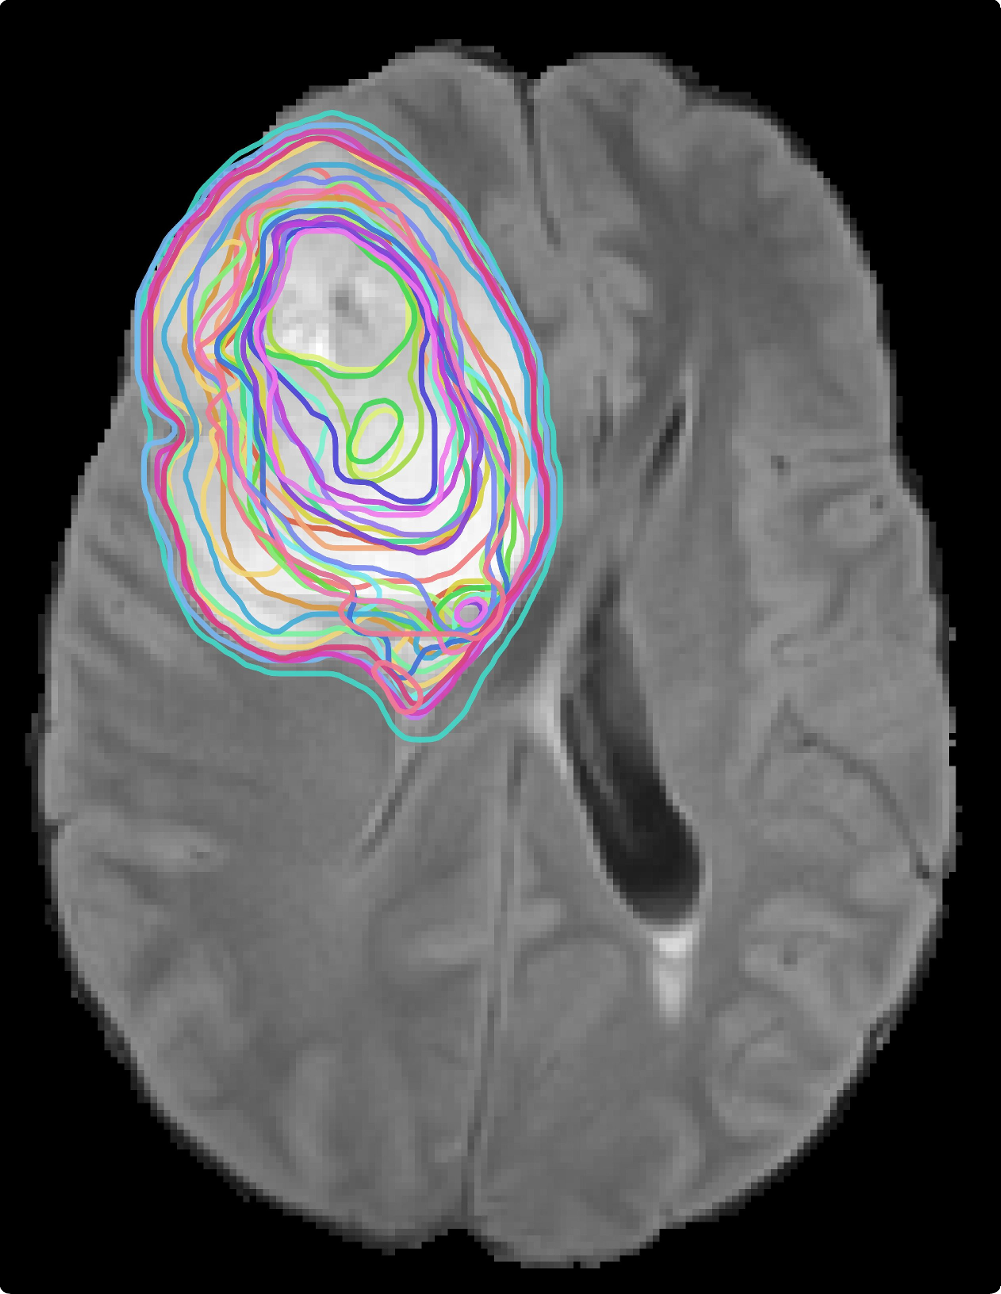

[A slice of the T1 image]

[A soft mask slice]

[Spaghetti plots of thresholded soft masks]

[3D contour boxplots]

5.1 Brain MRI Segmentation Soft Masks

Our method is applied to ensembles of soft masks from a collection of segmentation models, as shown in Fig.˜8. We use a 3D brain tumor MRI dataset (T1/T1ce/T2/FLAIR)—MSD Tumour [antonelli2022medical]—with voxel-wise labels for four classes (background, necrotic/non-enhancing core, edema, enhancing tumor), as shown in Fig.˜8(a). The data has a spatial resolution of voxels. For the ensemble input to PID-mean, we train 31 SegResNet models under different initialization and training-stabilization configurations while keeping the architecture and augmentations fixed, then collect the soft mask outputs (one exemplary soft mask is shown in Fig.˜8(b)) of these 31 models on the same test data (Fig.˜8(c)). Details of the data preparation are covered in the supplemental material [supplemental:ProbInclDepth].

Contour boxplots of 3D soft mask ensembles (thresholded at a probability of 0.5 to create surfaces) are sorted by PID-mean and visualized in Fig.˜8(d). Refractions highlight fine details of the complex shapes of the brain tumor. It can be seen that the envelopes of 50% members (orange) and 100% (blue) members are largely identical but differ in several locations on the outer boundaries, while the median member (yellow) is inside the band of 50% members. Due to color blending, the inner surface of the 100% members band in blue appears light emerald green, and this holds for other examples in the section too.

The contour boxplot can help with segmentation quality control for soft masks. Low-depth contours identified by PID-mean can effectively flag high-risk or outlier segments for review, whereas high-depth contours indicate the typical segment from the collection of segmentation networks. By further examining the associated soft masks, one can improve the settings of the segmentation model for desired results.